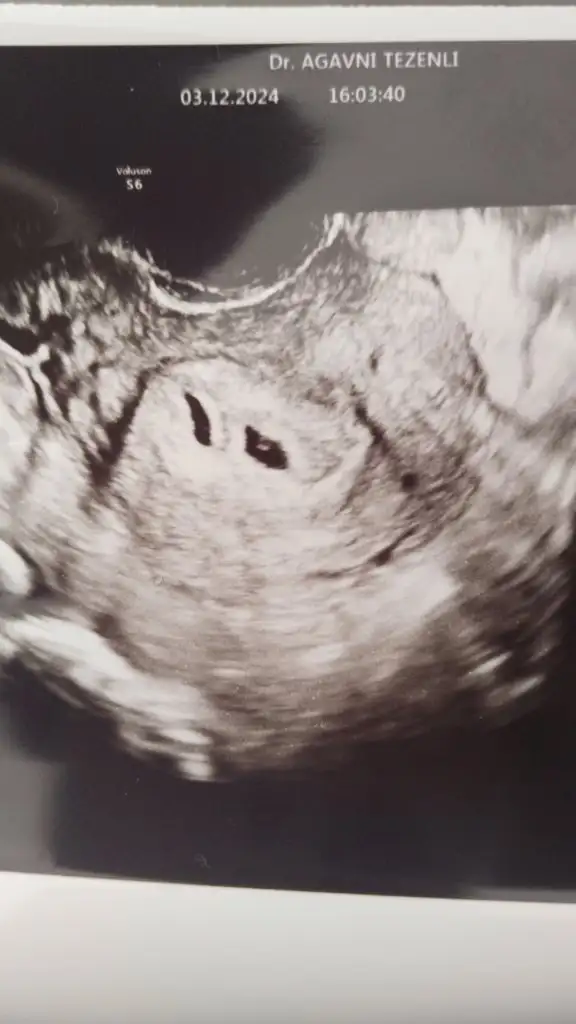

Teşekkür ederimbak buradalar iki kese de dolu doktor gördü şükür rabbim hepimizin yardımcısı olsun hep dua edelim

Maşallah minnoşlar siziTeşekkür ederimbak buradalar iki kese de dolu doktor gördü şükür rabbim hepimizin yardımcısı olsun hep dua edelim

Oyyy maşallahTeşekkür ederimbak buradalar iki kese de dolu doktor gördü şükür rabbim hepimizin yardımcısı olsun hep dua edelim